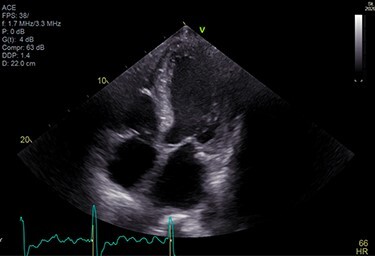

A 71-year-old male presented with DOE and syncopal episodes. His past medical history (PMH) was notable for hypothyroidism, hypertension (HTN), type II diabetes mellitus, obstructive sleep apnea (OSA), CTS, CHF, stage IV chronic kidney disease (CKD IV), complete heart block post-successful permanent pacemaker, paroxysmal atrial fibrillation (AFib). Labs were significant for mildly elevated troponin I (TnI) 0.12 ng/ml, elevated NT-proBNP 9655 pg/ml. EKG showed no acute ST-T changes. Transthoracic echocardiogram (TTE) was suggestive of infiltrative cardiomyopathy (Fig. 1).

Figure 1 .

A TTE showing homogenous speckled myocardium.